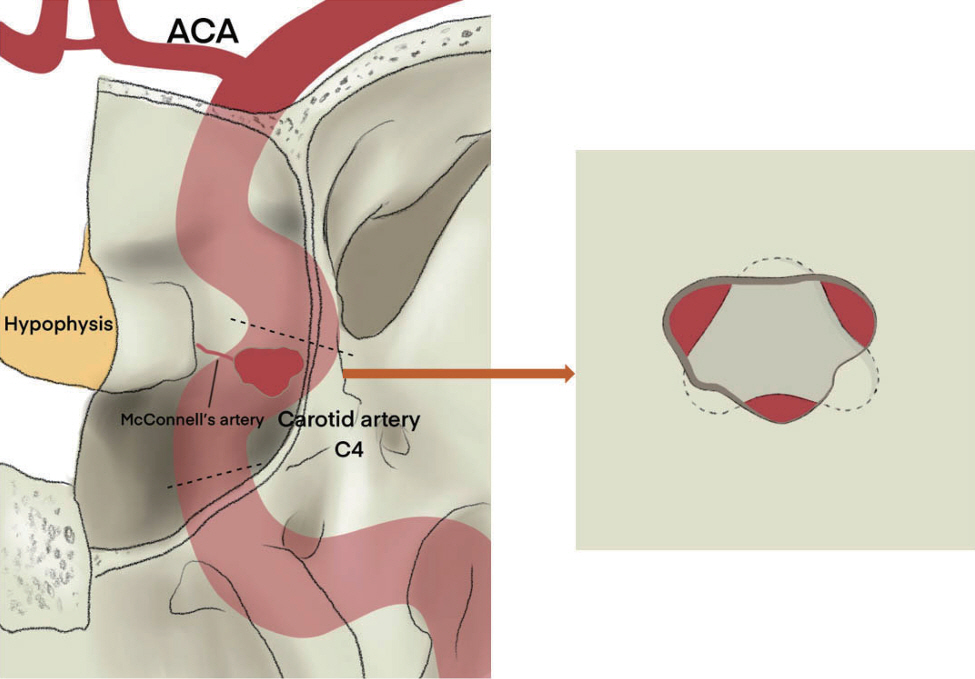

A Successful Control of the Intraoperative Bleeding from McConnell’s Artery during Fully Endoscopic Resection of Planum Sphenoidale Meningioma Using Bone Chip and Bioglue : A Case Report

- The endoscopic transsphenoidal approach is a common approach used in skull base neurosurgery to reach the sellar region. One of the intraoperative risks of this approach is intraoperative bleeding out of the carotid artery. Gentle drilling can prevent carotid artery injury. However, injury to smaller branches, such as the McConnell’s capsular artery, which is located within the surgical corridor, is more difficult to prevent. If such an injury is within the junction to the main trunk of the carotid artery, there will be a small circular defect in this area. This can result in massive blood loss and should be closed surgically immediately. We describe a clinical case of intraoperative bleeding from the McConnell’s artery originating from the carotid arterial segment (C4) in a 78-year-old female patient operated on for planum sphenoidale meningioma via endoscopic transsphenoidal approach, as well as provide a technical note on a possible technique for bleeding control in such cases. Pinpoint carotid bleeding as a result of intraoperative injury can be stopped by wedging a bone fragment in the carotid canal and fixing it in that position with histoacryl glue at the defect site.